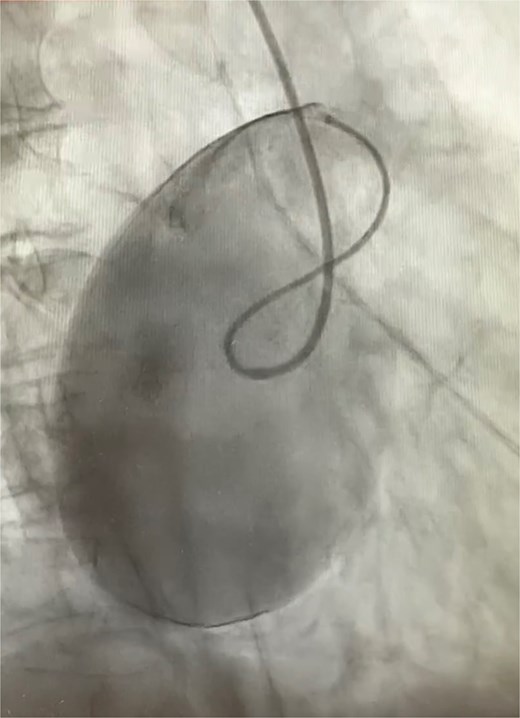

An 82-year-old female presented to the emergency department complaining of progressive severe central chest that was pleuritic in nature, radiating to her right arm. Following a bedside echo, the patient underwent coronary angiography, where a giant right CAA was diagnosed (Fig. 1). Subsequent, contrast computed tomography (CT) scan further characterized the aneurysm, and highlighted significant compression was uncovered compressing both the right atrium and ventricle (Fig. 2). The right coronary aneurysm was measured cross-sectional dimensions of 8.3 × 7.4 cm (Fig. 3) and 10 cm in length (Fig. 4). Following Heart Team discussion, the patient was scheduled for an aneurysmectomy and coronary artery bypass to repair the extensive disease.